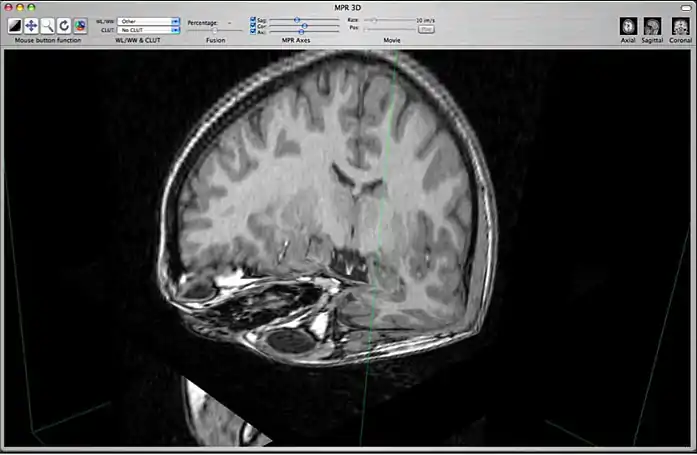

c) 3D Orthogonal MPR

3D orthogonal MPR mode

This mode allows you to display a 3D representation of the volume with 3D orthogonal MPR slices. You can change the position of the orthogonal slices by using the 3 sliders located in the toolbar: